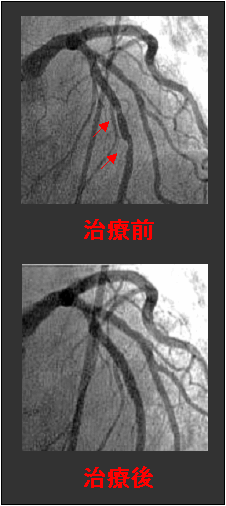

人間の生命活動を血液の循環を通じて支える心臓、そして血管。それだけに、心臓病は深刻な問題になります。現在では動脈硬化疾患である心疾患と脳血管障害が日本の死因の第2位、3位を占めています。 当院では、増加し続ける循環器疾患の治療部門において、医師、看護師、臨床検査技師、放射線技師が24時間体制で待機し、昼夜を問わず、対応しています。 心臓カテーテル検査は、大腿動脈もしくは肘動脈より血管造影用カテーテルを挿入し、冠動脈を撮影する事を目的としています。 造影の結果、狭窄部位が発見されれば、冠動脈血管内エコー(IVUS)検査により、その部位の治療の必要性を判断し、経皮的冠動脈形成術(PTCA)、冠動脈内ステント留置術

、至適インターベンション法の選択を行っています。バイパス治療(冠動脈血行再建術)においては鹿児島大学に依頼しています。 また、画像診断、カテーテル治療の質の向上さらには、被曝量低減を実現するため、2004年6月より、世界初の直接変換型フラットパネルシステム「DEGITEX Safire」を導入しました。鮮明な冠動脈の視認性を確保し、より正確な治療ができるよう万全の体制を整えています。 |